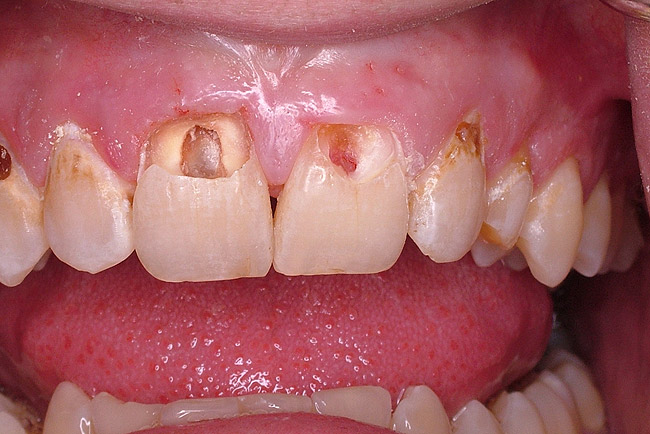

Figure 9A Deep Class V caries (pulpal vitality test: no response).

Figure 9A

Figure 9B Removal of caries tooth Nos. 8 and 9 reveals nonvital pulp.

Figure 9B